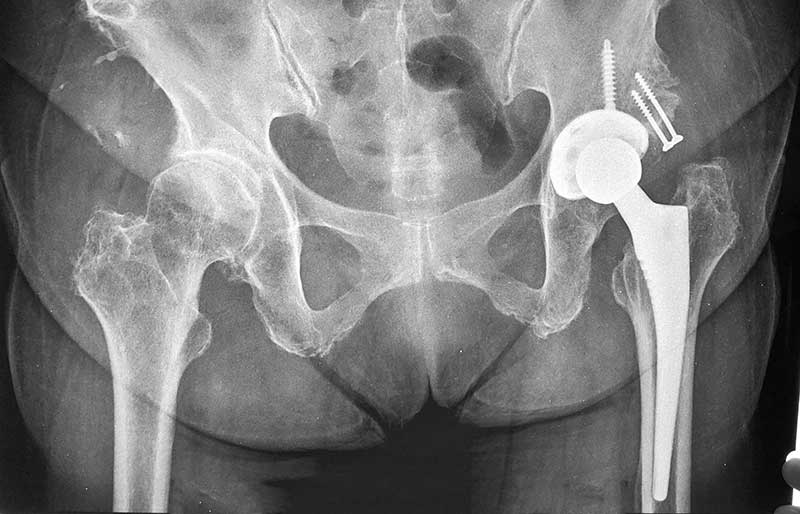

Operasi Penggantian Sendi Panggul

Operasi penggantian sendi panggul adalah suatu operasi untuk mengganti sendi panggul yang rusak dengan sendi buatan yang disebut prosthesis. Penyebab utama kerusakan sendi panggul adalah osteoartritis (baca penjelasan tentang “Osteoartritis”) dan sendi panggul adalah sendi terbanyak kedua setelah lutut yang terserang penyakit ini.

Operasi penggantian sendi panggul merupakan pengobatan terbaik untuk osteoartritis panggul stadium yang berat. Ada empat tujuan operasi ini, yaitu menghilangkan rasa sakit sendi yang telah rusak, memperbaiki lingkup gerak sendi yang sebelumnya kaku dan terbatas, mengembalikan kemampuan penderita melakukan aktivitas harian tanpa rasa sakit, dan meningkatkan kualitas hidup sehingga penderita kerusakan sendi dapat menjalani hidup secara aktif bebas dari nyeri sendi panggul.